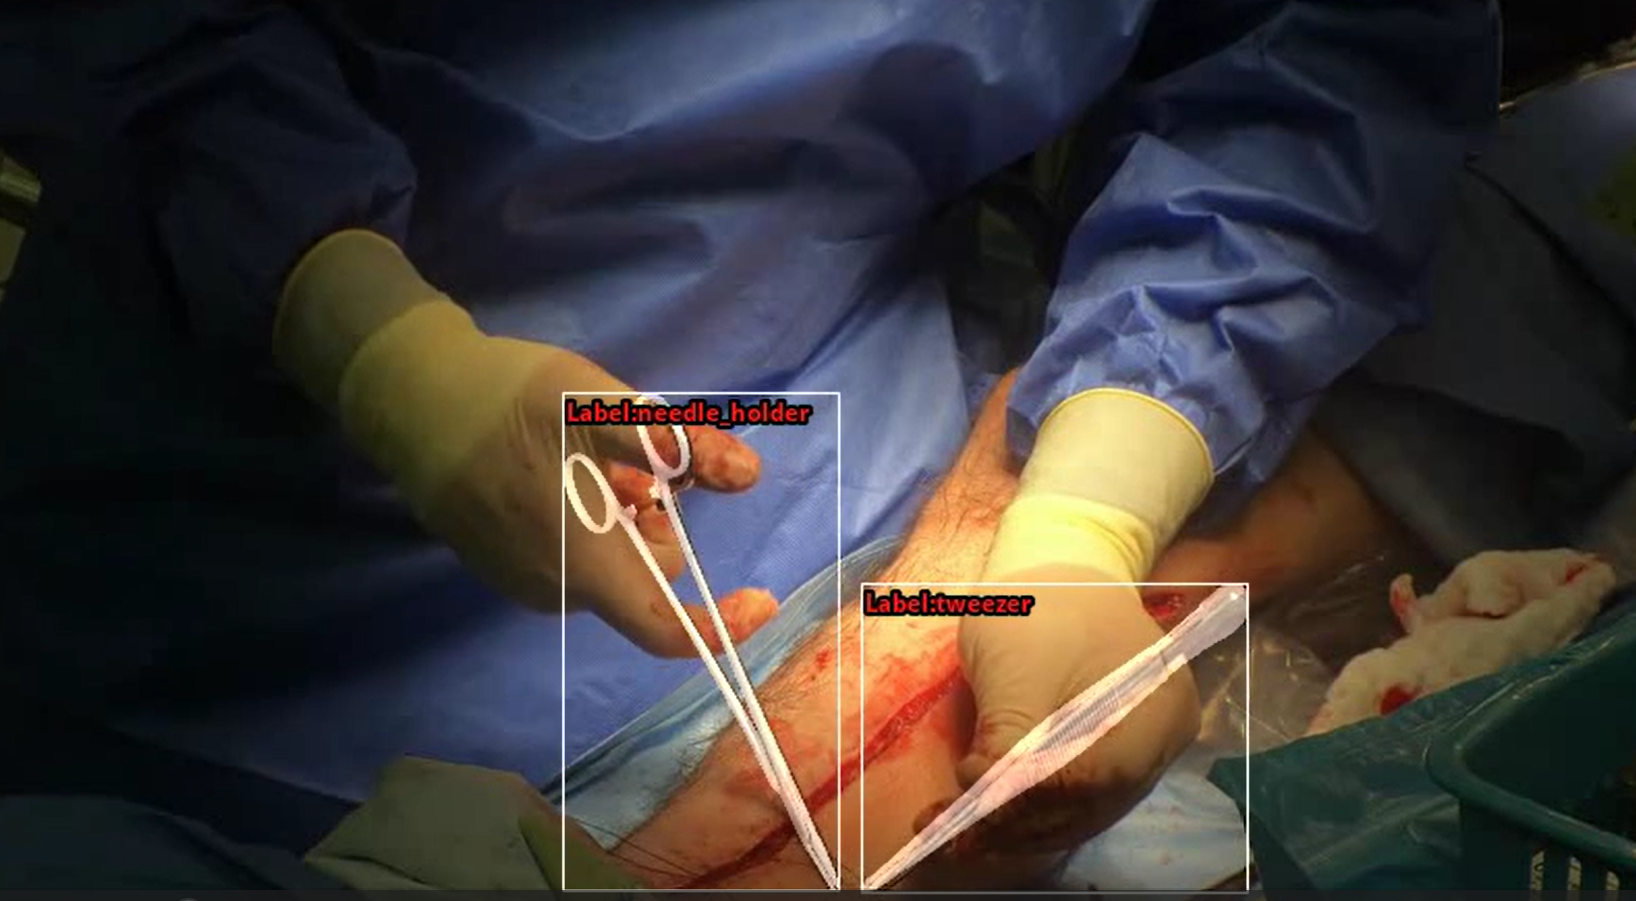

The dataset is annotated at multiple levels. We provide frame-level labels of surgical gestures, enabling fine-grained analysis of actions such as needle insertion, gripping, and passing. In addition, we generate detailed segmentation masks of surgical tools and hands, which are used for both evaluation and model development. Beyond these annotations, our pipeline derives richer representations from the data, including 6D tool pose and 3D hand pose, allowing us to move beyond raw video toward a structured understanding of surgical activity.

We developed a novel framework for monocular 6D pose estimation of articulated surgical instruments in open surgery. The goal is to recover, from a single RGB video stream, the full spatial configuration of surgical tools, including their position, orientation, and articulation.

A key challenge in this problem is the lack of annotated real-world data. To address this, we developed a synthetic data generation pipeline based on 3D scanning of surgical instruments and physically based rendering. This approach enables the creation of large-scale, fully annotated datasets that capture realistic variations in tool appearance, articulation, and interaction with the surgeon’s hands.

Building on this data, we designed a dedicated pose estimation framework that jointly predicts tool pose, category, and articulation. The model is further refined using domain adaptation techniques that leverage unlabeled real surgical videos, effectively bridging the gap between synthetic and clinical data. Importantly, this approach eliminates the need for manual annotation of real surgical images and allows new tools to be incorporated using only their 3D models.

The resulting system demonstrates strong performance on real surgical procedures, despite challenges such as occlusions, reflective surfaces, and complex tool geometries. This makes it a practical foundation for downstream applications, including surgical navigation, augmented reality, and robotic assistance.

3D Reconstruction of Surgical Instruments – Synthetic Data

Needle Holder Needle Holder |

Tweezers Tweezers |